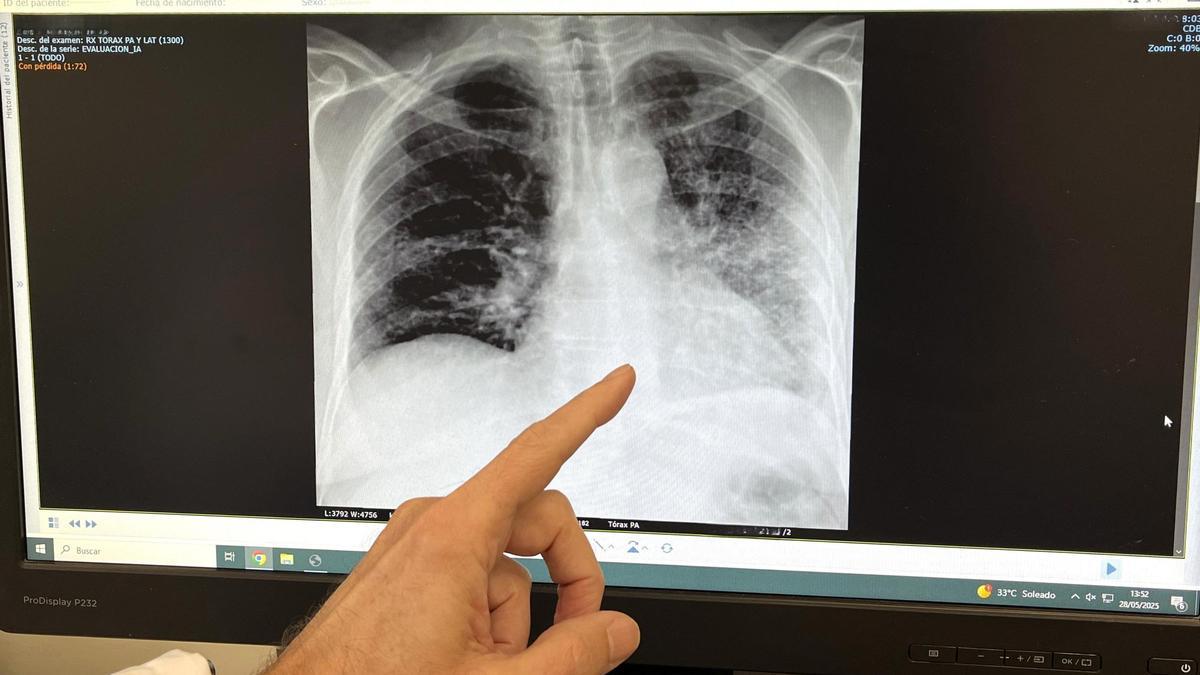

Foto RX paciente fumador con cáncer de pulmón. / CÓRDOBA

El tabaco es el responsable de más del 85% de los casos de cáncer de pulmón, así como de enfermedades como la Enfermedad Pulmonar Obstructiva Crónica (EPOC), bronquitis crónica y exacerbaciones del asma, según ha recalcado el doctor José Daniel Alcázar, jefe de servicio de Neumología del Hospital Quirónsalud Málaga. El doctor Alcázar ha afirmado que “en el Hospital Quirónsalud Málaga seguimos comprometidos con la prevención, el diagnóstico precoz y el tratamiento de enfermedades respiratorias vinculadas al tabaco”. Gracias a la incorporación reciente de la técnica EBUS (ecobroncoscopia), “damos un paso más en la detección y estadificación de enfermedades pulmonares, incluyendo el cáncer de pulmón, de forma mínimamente invasiva y con la máxima precisión diagnóstica”.